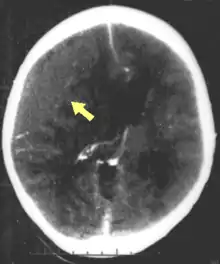

CT scan showing cerebral contusions, hemorrhage within the hemispheres, and subdural hematoma. There is also displaced skull fracture of left transverse parietal and temporal bones.[2]